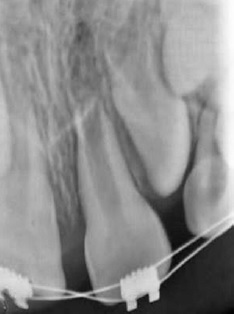

After one week, periapical radiography revealed the correct positioning of the tooth and a regular aspect of the root surfasse (Figure 3). Fifteen days after replantation, the splint was removed.

Figure 3 Periapical radiograph one week after the trauma, with the left maxillary central incisor (21) showing a regular root surface aspect.

The tooth did not respond to the cold test (1,1,1,2-tetrafluoroethane-Endo Ice). All the other signs and symptoms were normal. Seven weeks after replantation, the color of the tooth crown appeared normal, suggesting potential pulp revascularization despite the negative response to the cold test.

The periapical radiograph revealed no evidence of root resorption or periapical lesion.